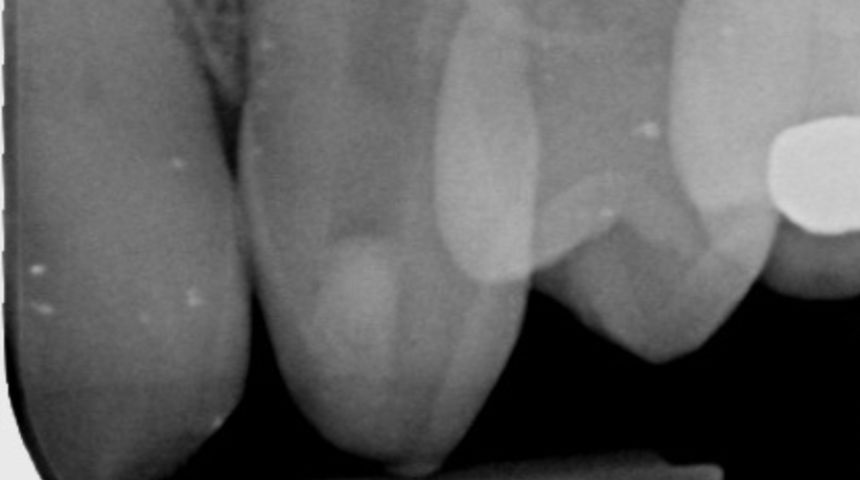

Take a look at some of our recent cases below!